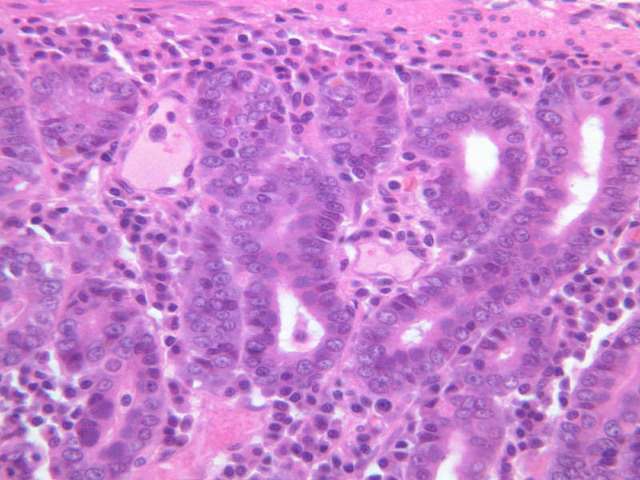

The glands of the stomach exhibit regional variations in size, form, and cellular composition. The glands of the cardia (slide B-1) and pylorus (slide B-9) are coiled, often branched tubules that that are associated with very deep gastric pits and consist almost entirely of mucous-secreting cells. In the gastric fundus (slide B-4, H&E [2.5x, 10x, 20x, 40x] [10x, 20x, 40x-labeled] [40x]) and corpus (slides B-5, H&E [2.5x, 10x, 20x, 40x] [10x, 20x, 40x] [40x] & B-6, PAS [2.5x, 10x, 20x, 40x]), the glands are relatively straight and are known as fundic glands or gastric glands; they are made up of mucous neck cells, chief cells, parietal cells, and APUD cells. The lumina of fundic glands are much less evident than are those of cardiac and pyloric glands. Study slides B-4, 5 & 6 to familiarize yourself with the cell types found in fundic glands.

The chief or zymogenic cells have a rather granular, basophilic cytoplasm and produce pepsinogen, which, upon encountering the acidic gastric juice, is converted into the proteolytic enzyme pepsin. As the name suggests, the chief cells are usually the most numerous cell type in the glands of the fundic region.

The parietal cells are large and have conspicuously acidophilic cytoplasm. They are the source of both gastric HCl. and intrinsic factor, which is necessary for uptake of vitamin B12 in the ileum. The fine structure of parietal cells shows that their cytoplasm is filled with a very large number of surface invaginations or secretory canaliculi, which, in turn, are covered with microvilli. It is apparently this elaboration of surface area that allows parietal cells to secrete large amounts of HCl. Why are parietal cells eosinophilic?